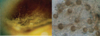

Descripcion de cultivo y de imagen hace sugestivo el diagnostico de:

Aspergilus nidulans

Colonias polvorosas, amarillentas con pequeño halo blanco(micelial)

Septos hialinos con conidios que nacen de fialides angulo de 140° grados

Celulas redondas que se llaman celulas de Hülle(celulas de avellana)